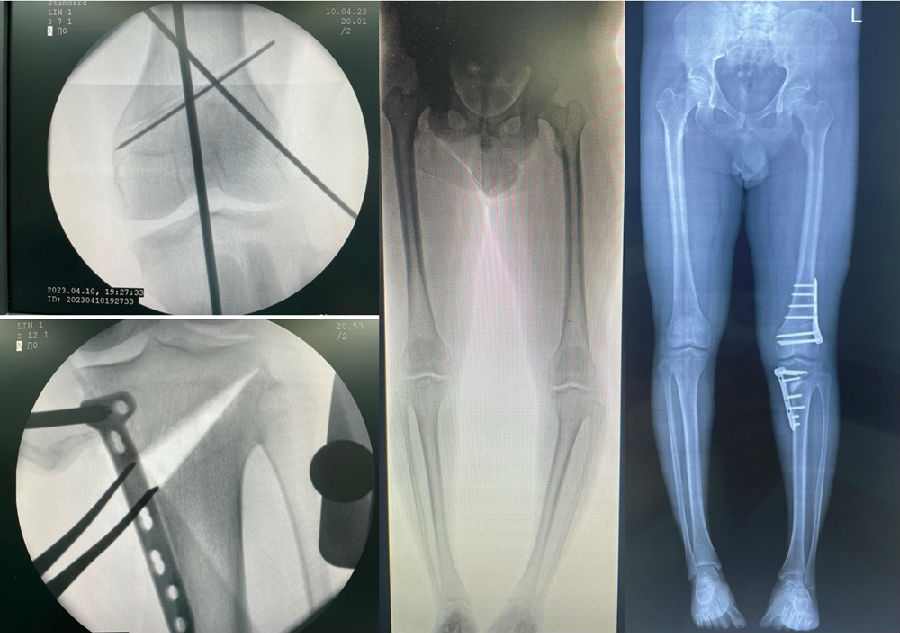

术后影像